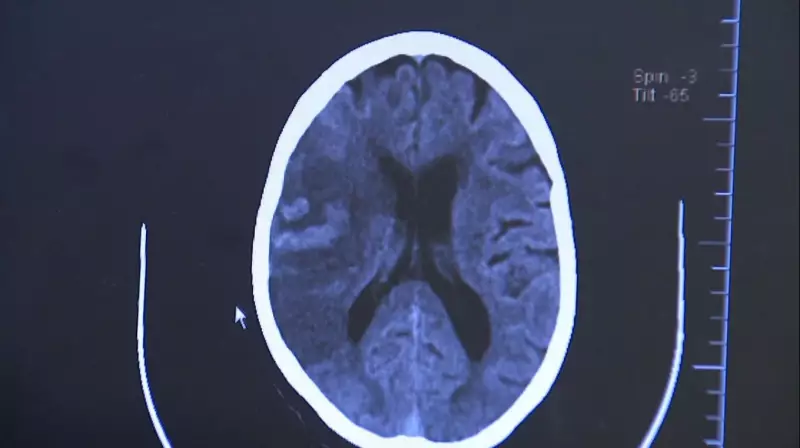

O Acidente Vascular Cerebral, popularmente conhecido como derrame, ocorre quando há interrupção do fluxo sanguíneo para o cérebro. Existem dois tipos principais:

- AVC Isquêmico: Quando um coágulo obstrui uma artéria

- AVC Hemorrágico: Quando ocorre ruptura de um vaso sanguíneo